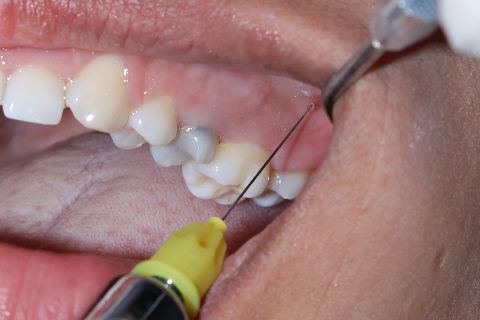

Anestesia infiltrativa